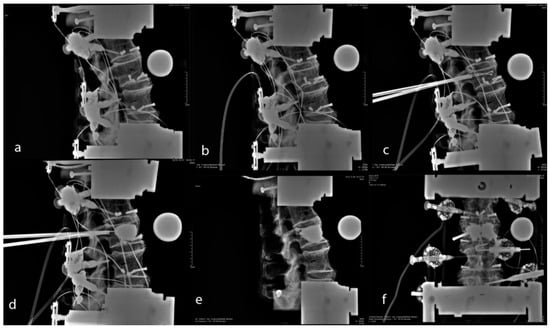

2.2. Fracture Creation

2.3. Kyphoplasty